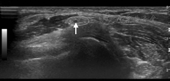

患者男,19岁,主动节食3个月余,体重由之前的73 kg降至64 kg,体质指数(BMI)由之前的24.4降至21.4。入院前2个月出现右足第1、2二脚趾麻木,渐进性加重,曾服中药治疗未见好转。就诊时扩大至整个足背,无下肢疼痛,伴右足下垂(图1)。否认外伤史和长时间盘腿病史,否认近3个月感冒史。体格检查:跨阈步态,颈、胸、腰部无压痛及叩击痛。右足背区麻木,右胫骨前肌、右踇长伸肌肌力0级。其余皮肤感觉及肌力正常。双侧"4"字试验阴性,双侧直腿抬高试验80°阴性。双侧腓骨颈远端2 cm处Tinel征阳性。双侧膝腱反射、跟腱反射活跃。髌阵挛、踝阵挛未引出。双侧Hoffmann征阳性。双侧Babinski征阴性。体格检查:颈椎、胸椎、腰椎、右膝MRI、脑CT未见明显异常。彩色多普勒超声检查(图2):双侧腓总神经回声完整连续,右侧腓总神经内可见单支神经束肿胀增粗(红箭头所示),内部回声减低,内径1.5 mm,以腓骨小头外侧增粗明显。左侧腓总神经内未见明显肿胀增粗表现。诱发电位和肌电图研究:(1)运动及感觉检查:电刺激右踝水平,显示4.4 ms潜伏期和7.7 mV波幅;电刺激腓骨小头下1.5 cm显示9.7 ms潜伏期和0.1 mV波幅,传导速度62 m/s;电刺激腓骨小头上1.5 cm显示11.2 ms潜伏期和0.1 mV波幅,传导速度27 m/s。提示腓总神经于腓骨小头上下神经传导速度减慢(降低约53%),波幅减低(约为正常值的98%);右侧腓总神经感觉传导未引出肯定波形。右腓浅神经运动传导,右胫后神经运动感觉传导未见明显异常。(2)肌电图检查:右侧胫骨前肌肌电图示插入电位增加,运动单位电位时限增加(Dur=16.8 ms),提示神经源性损害;右侧腓骨长短肌、腓肠肌肌电图未见明显异常。(3)刺激右侧胫后神经H反射未见明显异常。化验检查血常规白细胞:8.29 (3.5~9.5)×109/L;中性粒细胞比率:33.2%(40%~75%);淋巴细胞比率:55.6%(20%~50%);淋巴细胞数:4.61(1.1~3.2)×109/L;单核细胞数:0.8(0.1~0.6)×109/L;红细胞压积:0.39(0.4~0.5) L/L;生化常规前白蛋白:191 (220~440) mg/L;高密度脂蛋白胆固醇:0.79 (0.93~1.81) mol/L;低度脂蛋白胆固醇:1.88 (2.07~3.63) mol/L。治疗:恢复平衡饮食并给予神经营养因子和B族维生素治疗,1.5个月后,患者体重增加2.5 kg,患肢踇长伸肌肌力恢复为3级,胫骨前肌肌力恢复为4级。复查肌电图显示,电刺激腓骨小头下1.5 cm,显示9.1 ms潜伏期和3.3 mV波幅,传导速度为68 m/s;电刺激腓骨小头上1.5 cm,显示10.4 ms潜伏期和3.3 mV波幅,传导速度为62 m/s。可见腓骨小头处的波幅和传导速度均有明显改善。患者感觉症状改善明显。